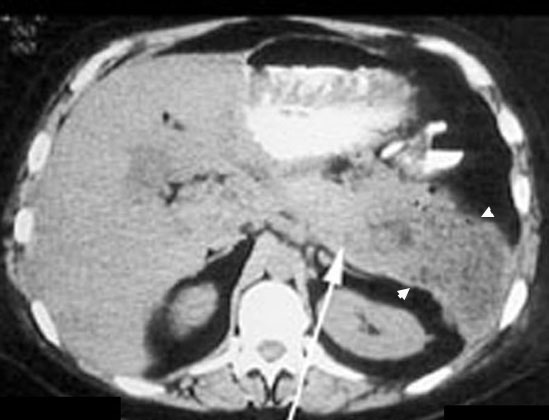

Pancreatic

Pancreatic abscess

Diffusely enlarged pancreas with air pockets.

Arrow points to body of Pancreas

Abscess is in tail of Pancreas